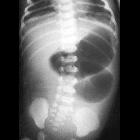

The classic radiographic sign of jejunal atresia is that of a triple bubble appearance for a proximal obstruction; it is equivalent to the double bubble sign of duodenal appearance plus a third bubble is caused by filling and distention of the jejunum by air.

There can be multiple dilated small bowel loops proximal to the atresia and the number of dilated loops increase as point of atresia becomes more distal.